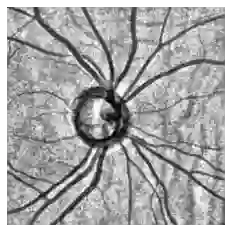

Fairness in artificial intelligence models has gained significantly more attention in recent years, especially in the area of medicine, as fairness in medical models is critical to people's well-being and lives. High-quality medical fairness datasets are needed to promote fairness learning research. Existing medical fairness datasets are all for classification tasks, and no fairness datasets are available for medical segmentation, while medical segmentation is an equally important clinical task as classifications, which can provide detailed spatial information on organ abnormalities ready to be assessed by clinicians. In this paper, we propose the first fairness dataset for medical segmentation named Harvard-FairSeg with 10,000 subject samples. In addition, we propose a fair error-bound scaling approach to reweight the loss function with the upper error-bound in each identity group, using the segment anything model (SAM). We anticipate that the segmentation performance equity can be improved by explicitly tackling the hard cases with high training errors in each identity group. To facilitate fair comparisons, we utilize a novel equity-scaled segmentation performance metric to compare segmentation metrics in the context of fairness, such as the equity-scaled Dice coefficient. Through comprehensive experiments, we demonstrate that our fair error-bound scaling approach either has superior or comparable fairness performance to the state-of-the-art fairness learning models. The dataset and code are publicly accessible via https://ophai.hms.harvard.edu/harvard-fairseg10k.